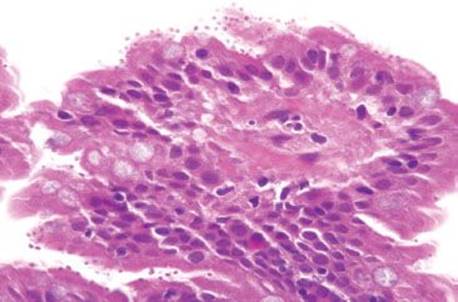

Figure 3.314 Infiltrating poorly-differentiated adenocarcinoma and lymphovascular space invasion. Deeper sections were performed until the block was exhausted. This photomicrograph represents the 38th (and final) section, which shows desmoplasia, infiltrating adenocarcinoma (arrowheads), and lymphovascular space invasion (asterisk). These deeper sections show an entirely different biopsy compared to the initial sections and were sufficient for chemotherapy initiation.

Figure 3.315 Sneaky adenocarcinoma involving the duodenal mucosa. Under oil immersion, note the nuclear irregularities, abundant pink cytoplasm, and cytoplasmic mucin droplet (arrowhead) characteristic of pancreatobiliary adenocarcinoma. Unfortunately, sometimes 38 levels are required for the ultimate diagnosis and sometimes only a few malignant cells are present! When the clinical scenario and the histology are not aligned, deeper sections (and deeper sections and deeper sections and deeper sections) are often required.